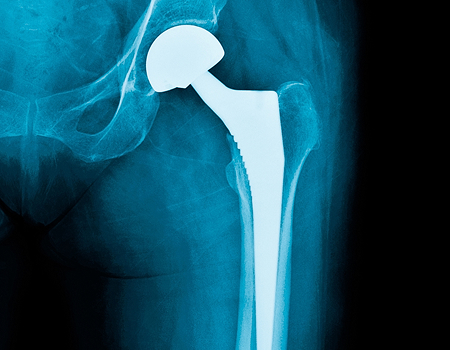

Hip Replacement Surgery